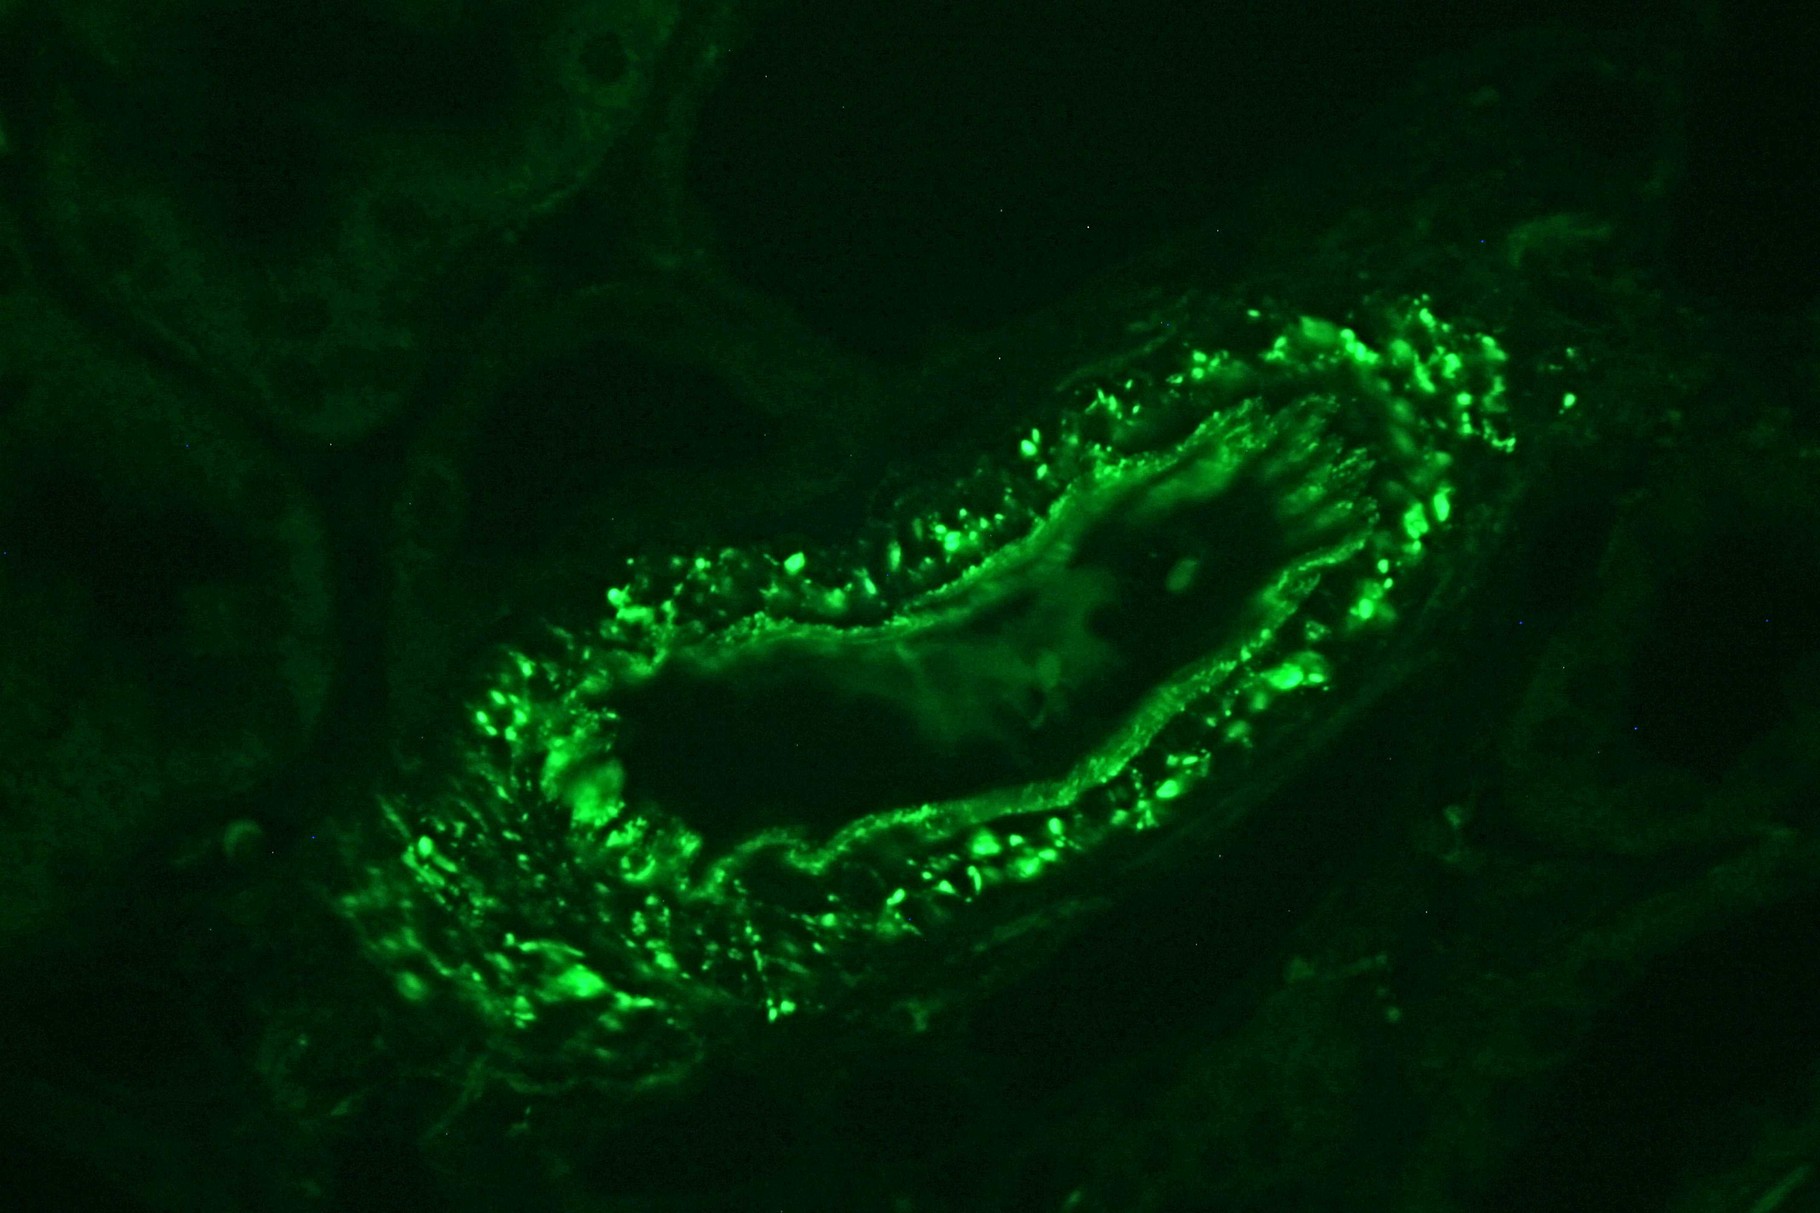

Patología Molecular

El diagnóstico sobre muestras de tejidos y líquidos corporales en plena era de la medicina del futuro, está basado en la integración de técnicas y conocimientos diferentes.

Hoy más que nunca es importante integrar una buena historia clínica con un correcto estudio de imagen y una buena morfología que además puede estar apoyada con proceso especiales complementarios relacionados con la Inmunología, Biología Molecular y Citogenética, generando así un estudio integral conocido como Patología Molecular.